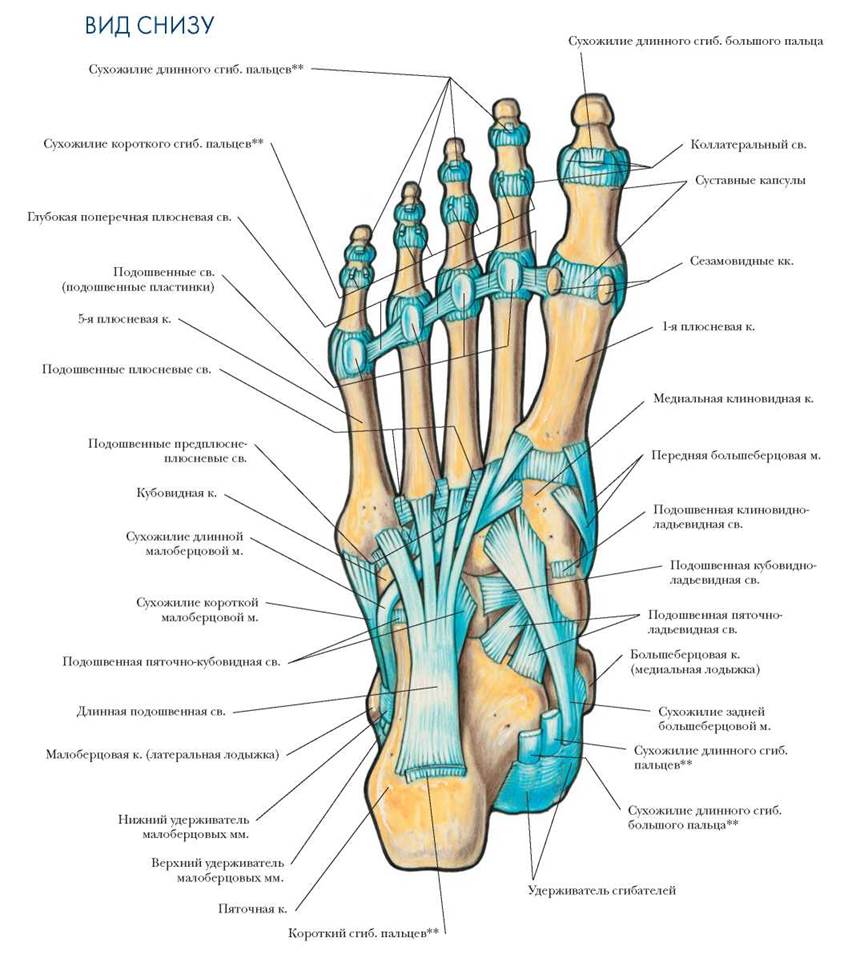

Анатомия суставов Шапарова и Лисфранка: фото и информация